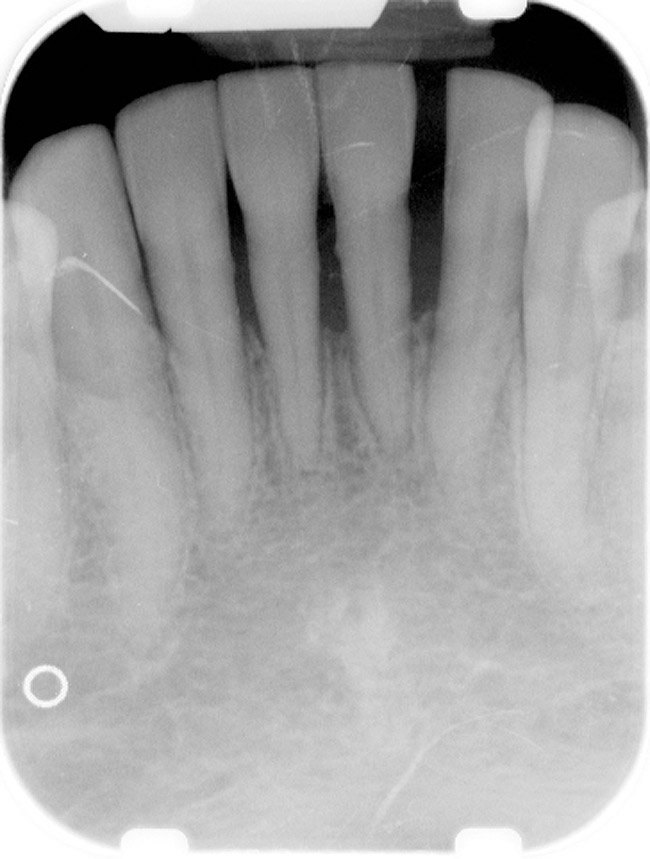

Under the sextant approach, one quadrant is treated and the patient is left to heal for 2 months before proceeding to any additional quadrants. While the patient heals, a 10-day course of antibiotics and 2 months of twice-daily chlorhexidine rinsing may be prescribed. Figure 4 shows a patient who was taking oral bisphosphonates for 3 years and was treated with the sextant approach. As seen in the radiograph, the patient has one molar in the lower right quadrant. This tooth was extracted and the patient was given 2 months to heal (Figure 5 and Figure 6). The patient was placed on antibiotics and chlorhexidine rinse. After 2 months, no signs of BRONJ were observed, and the anterior teeth were scheduled for extraction. They were extracted as atraumatically as possible, and the site was sutured (Figure 7 and Figure 8).The patient then was given another 2 months to heal, following the previous protocol. After 2 months of healing, no BRONJ was observed (Figure 9).

Figure 5  After 2 months of healing, the lower right quadrant showed no signs of BRONJ and the anterior teeth were scheduled for extraction.

Figure 5

Figure 6  After 2 months of healing, the lower right quadrant showed no signs of BRONJ and the anterior teeth were scheduled for extraction.

Figure 6

Figure 7  Anterior extraction sites after atraumatic removal.

Figure 7

Figure 8  Sutures were placed after extraction.

Figure 8

Figure 9  For this quadrant, no signs of BRONJ were observed after 2 months of healing.

Figure 9